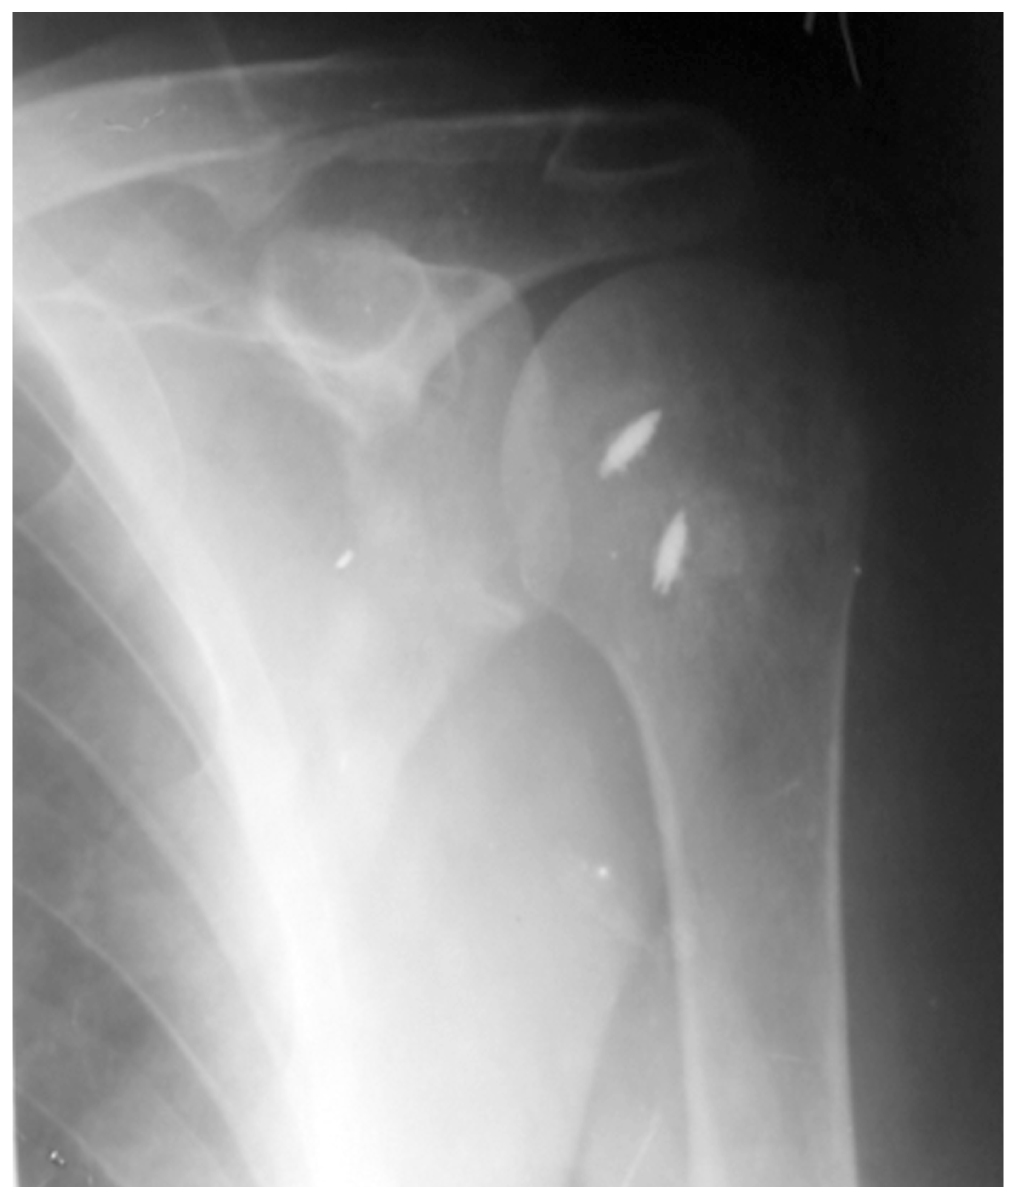

Based on the data from the clinical-instrumental examination, the diagnosis set was the following: “Long-standing engaged posterior dislocation of the humeral head, reverse Hill-Sachs fracture (osteochondral lesion in the anterior segment of the humeral head with an impression defect in the bone tissue with a defect area of 25% of the articular surface of the humeral head)”; Fig. 1.

Fig. 1. X-Ray of the shoulder joint of patient (direct projection) before surgery.